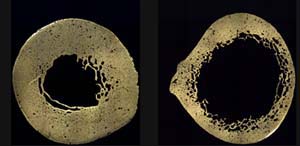

The femur cross-section on right shows significant reduction in bone thickness and reduced density near the inner surface.

These cross sections show the midshaft of the femur of an 84-year-old female with advanced osteoporosis (right), compared to a healthy femur of a 17-year-old female (left). Image Credit: Smithsonian National Museum of Natural History

Finally we have to subtract off the area of the hollow middle part to get the net bone area. We used a ruler on the above picture of the femur cross-sections to see that the inner radius is roughly half of the outer radius, or 5.85\, \times 10^{-3} \bold{m} so we calculate the missing inner area: